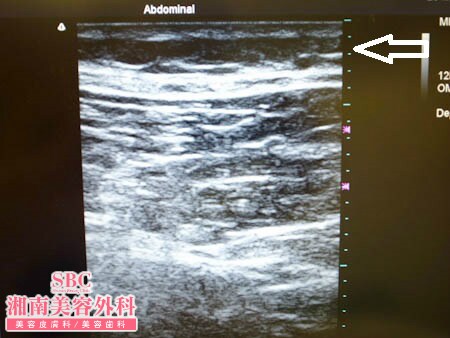

No.143258【脂肪吸引】脂肪吸引患者様数ダントツナンバーワンの実力がいまここに!〜遠方からご来院!1年半で45kg太ってしまった患者様の太ももを元に戻す!術中3Dタッチビュー〜